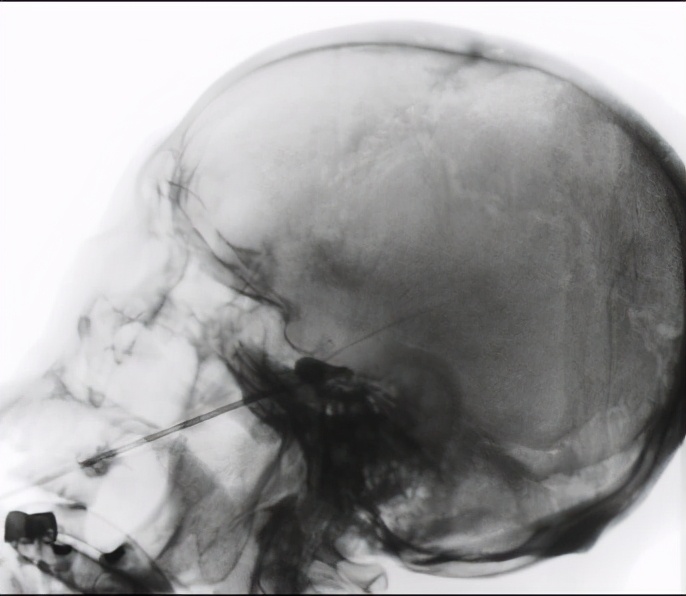

核酸检查阴性后住院了,疼痛科团队决定给何大爷做最新的国际报告打一针17年都不复发的三叉神经半月节球囊压迫镇痛术。但护士发现,何大爷手抖得有时连饭碗都抓不稳,测量血压升高到224mmHg,问他说平时的血压也一直是170、180的。检查脑MRI提示有脑梗塞、脑萎缩,心电图提示心肌明显缺血。

疼痛科医生在医院心血管科、麻醉科、手术室团队齐心协力帮助下,顺利给何大爷面部打了一针。拔针后10分钟麻醉醒过来,何大爷露出了久违的笑容,如同受酷刑般的痛苦消失得无影无踪。第2天他惊喜地告诉医生,说他看不到针口了,双手不再震颤了,血压也平稳在140mmHg左右了。

为解除这种折磨人的三叉神经痛,医学上1950年就使用射频破坏神经来镇痛。2020年卢主任在全国疼痛科最早引进了缝衣针般细的射频针穿刺帮助三叉神经痛病人。对畸形血管压迫,神经外科医生用开颅显微镜方法找到并隔开卡压神经的血管,达根治目的。卢主任团队的“对因治痛”原则,就是找到并松开神经旁边的卡压组织。这次给何大爷选择了打针,注射不到1ml的造影剂张开球囊,压迫神经镇痛的同时也推开了三叉神经根旁边的粘连组织,达长时间镇痛。